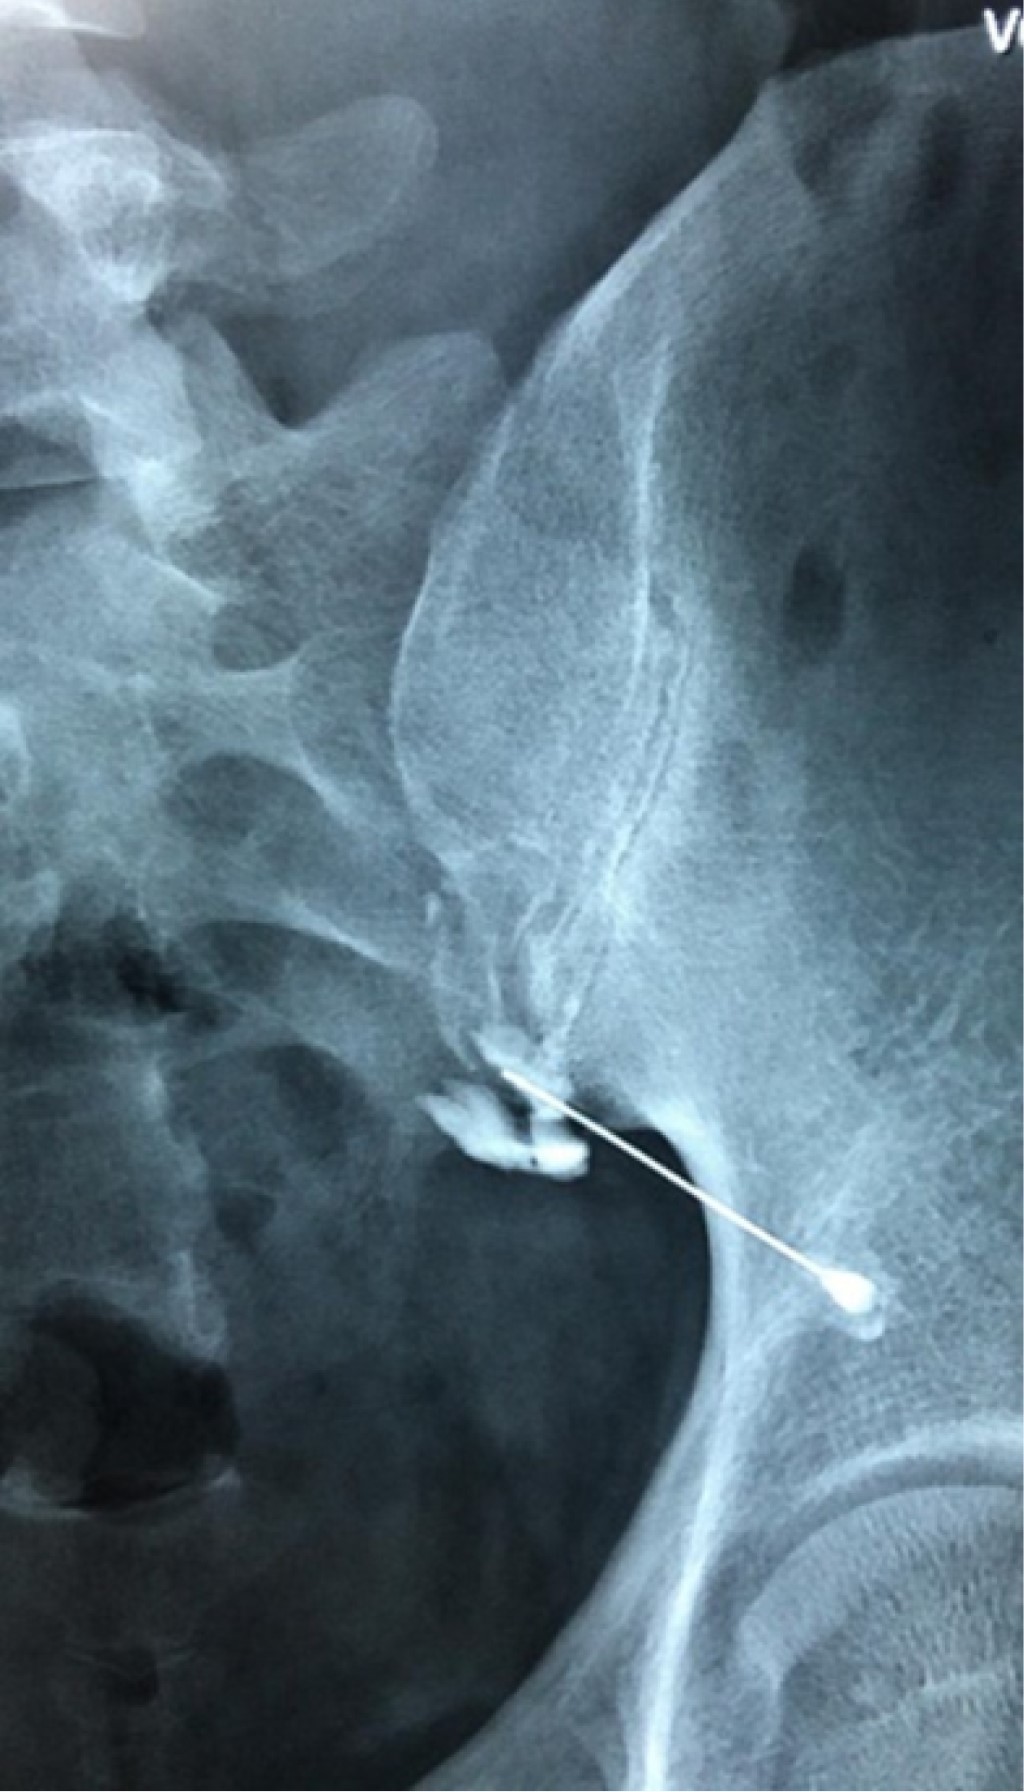

Figure 1

Figure 2

Figure 3

Figure 4

Figure 5

Figure 6

Figure 7

Figure 8

Figure 9